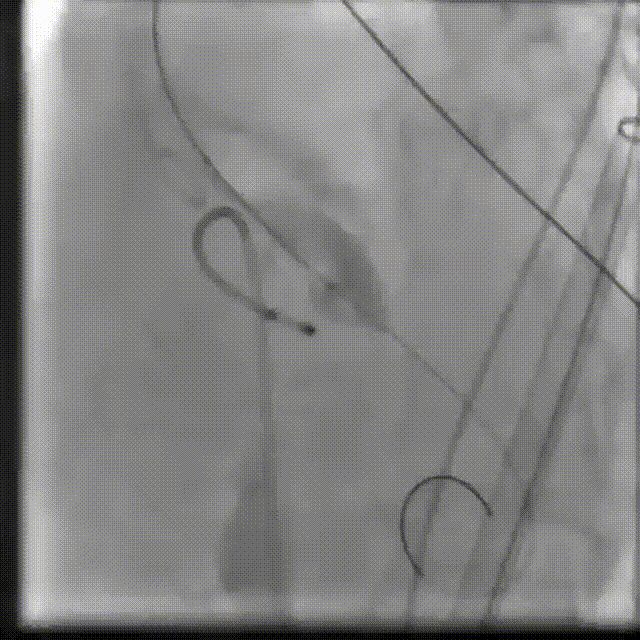

起搏心脏,预扩张主动脉瓣

球囊扩张

输送系统定位

瓣膜释放